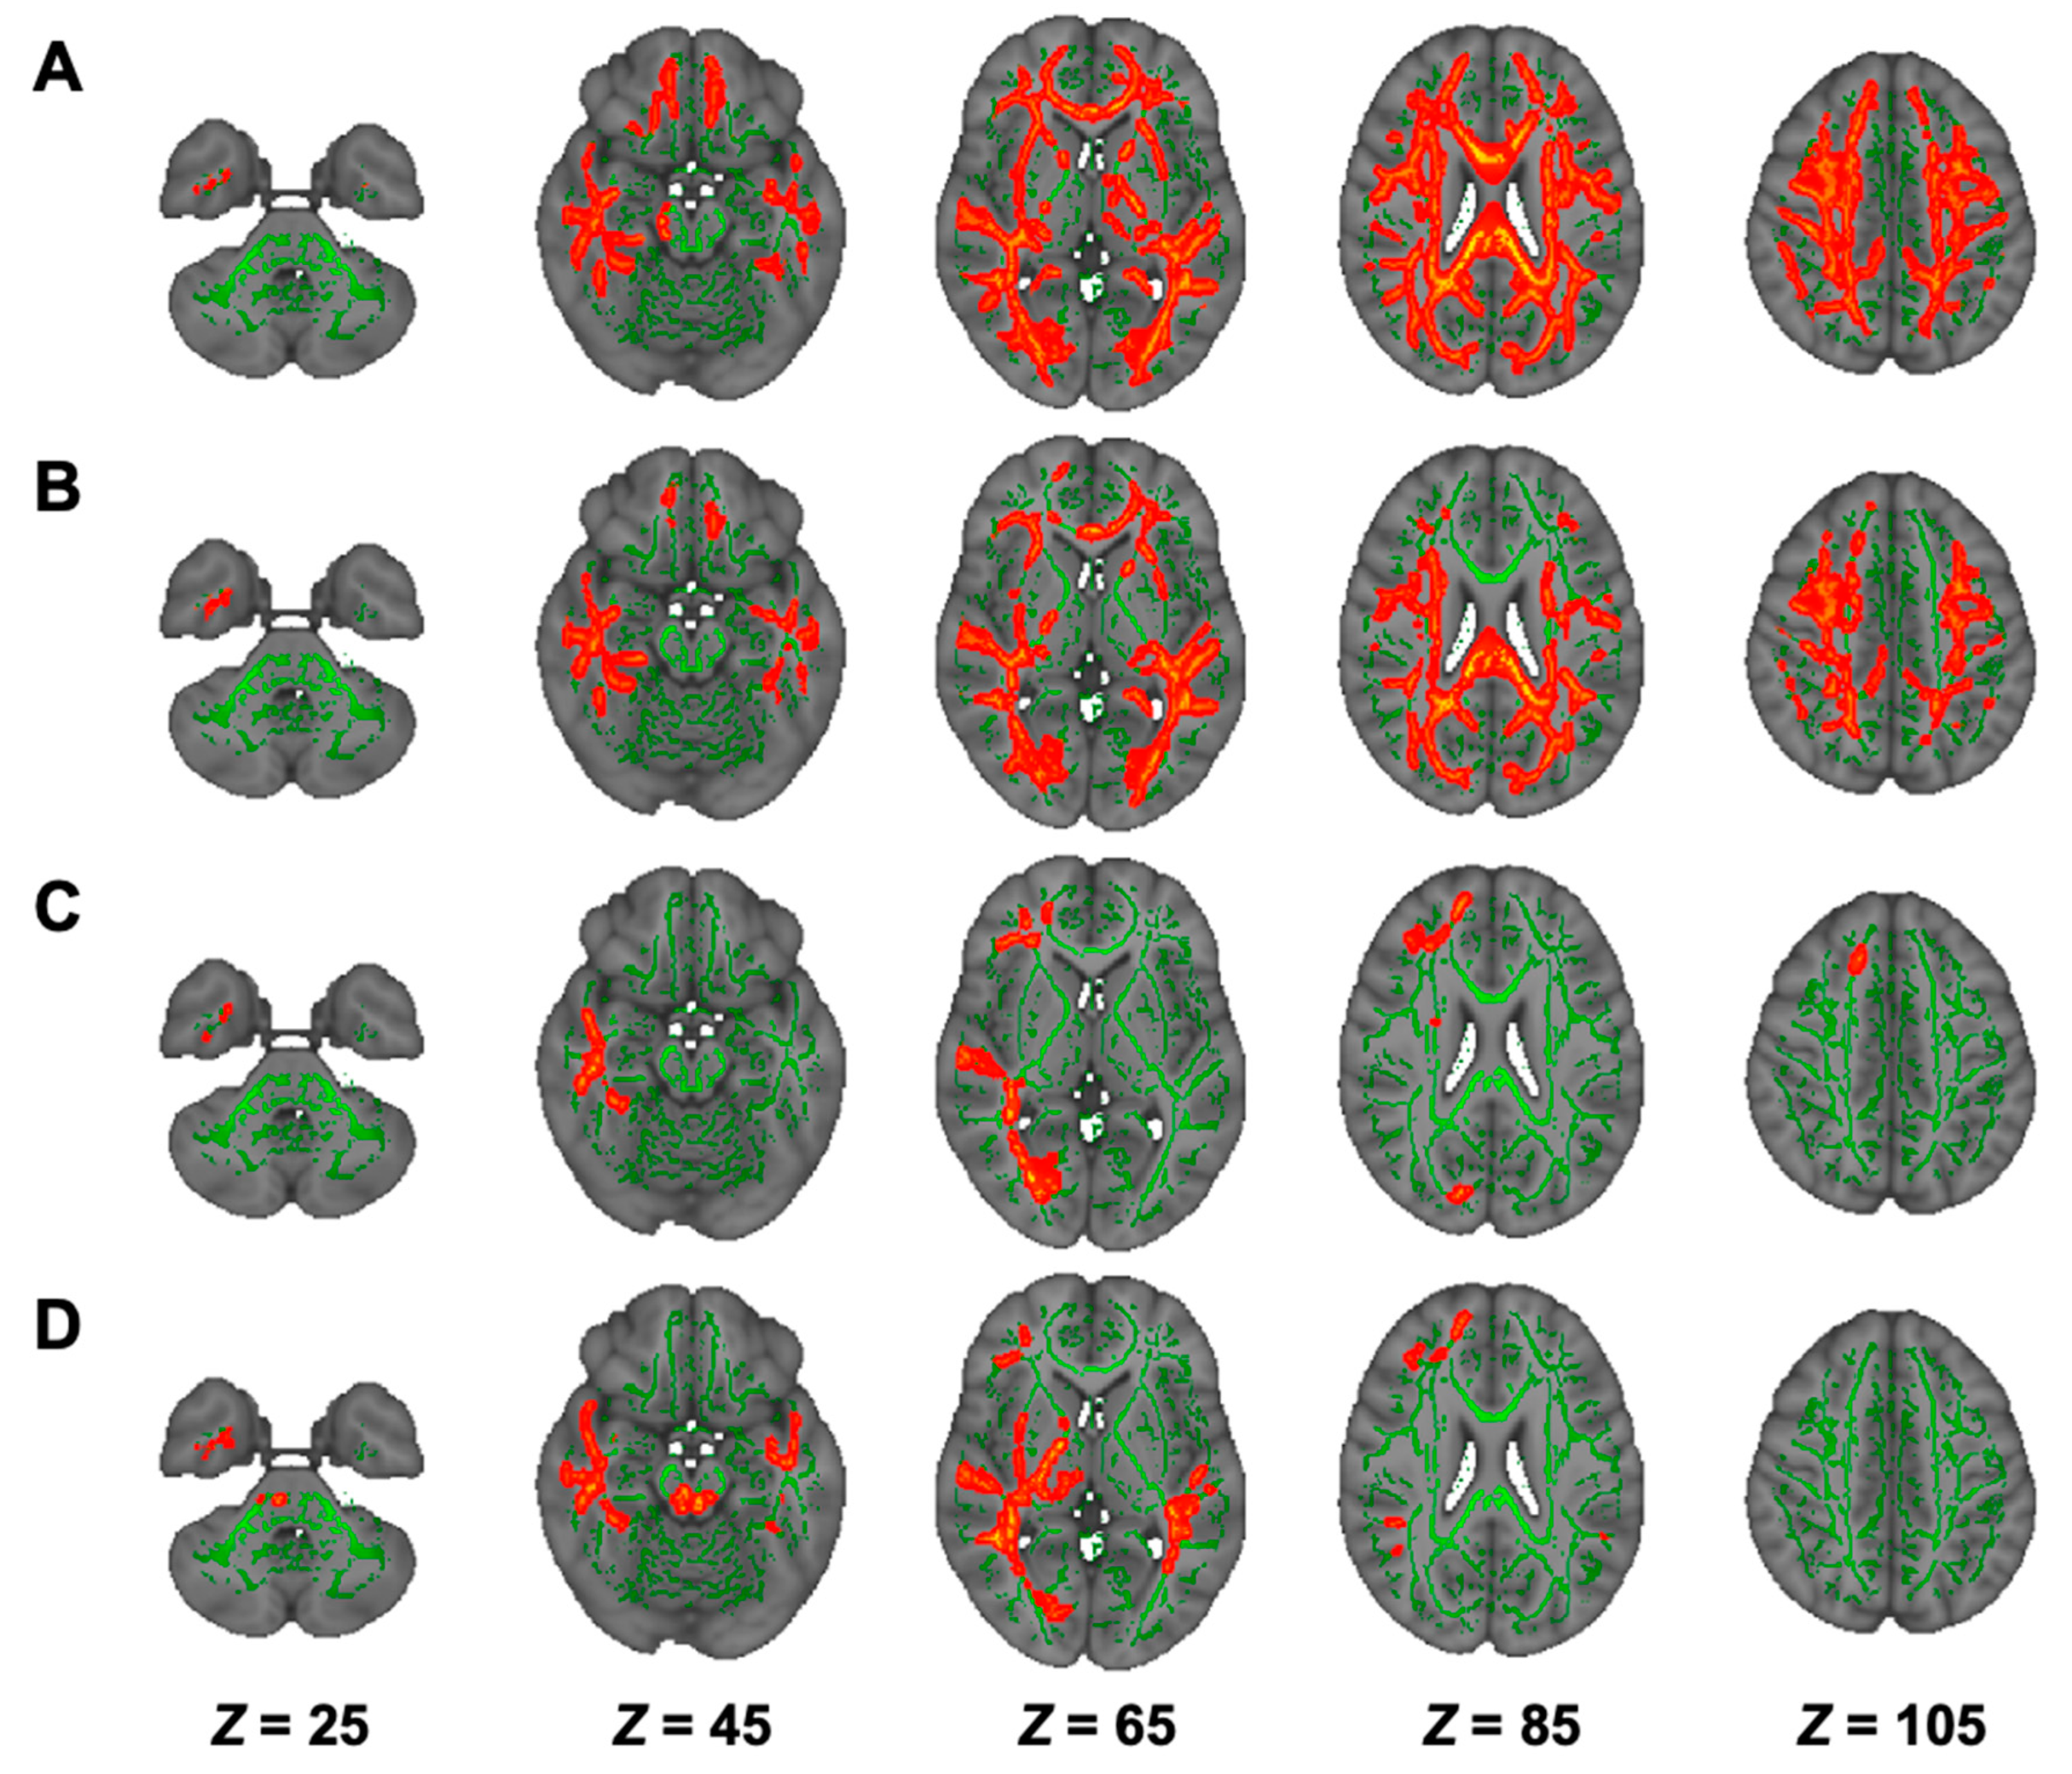

3.5. DTI Analysis in Hemodialysis Patients with NSTLC and LTLC

3.6. DKI Analysis in Hemodialysis Patients with NSTLC and LTLC

3.7. NODDI Analysis in Hemodialysis Patients with NSTLC and LTLC

| Modality | Contrast | Cluster Size | Anatomical Region | Peak t-Value | Peak MNI Coordinates (X, Y, Z) |

|---|---|---|---|---|---|

| DTI | |||||

| FA | HC > NSTLC | 48,825 | Bilateral ATR, corticospinal tract, CCG, forceps minor and major, IFOF, ILF, SLF, SLF temporal part, medial lemniscus, CP, ALIC, PLIC, retrolenticular part of IC, ACR, SCR, PCR, PTR, SS, external capsule, fornix stria terminalis, SFOF, tapetum; left UF, corticospinal tract, ICP, UF; right SCP; MCP, pontine crossing tract, genu, body and splenium of CC, fornix | 6.74 | (74, 69, 105) |

| AD | HC < NSTLC | 10,699 | Bilateral ATR, corticospinal tract, IFOF, SLF, ALIC, PLIC, retrolenticular part of IC, ACR, SCR, PCR, PTR, external capsule, fornix stria terminalis, SFOF; left ILF, SS, tapetum; forceps minor, UF, genu, body and splenium of CC, fornix | 5.85 | (50, 125, 100) |

| RD | HC < NSTLC | 49,556 | Bilateral ATR, corticospinal tract, CCG, IFOF, ILF, SLF, UF, SLF temporal part, CP, ALIC, PLIC, retrolenticular part of IC, ACR, SCR, PCR, PTR, SS, external capsule, fornix stria terminalis, SFOF, tapetum; forceps minor and major, genu, body and splenium of CC, fornix | 7.43 | (140, 117, 50) |

| MD | HC < NSTLC | 43,676 | Bilateral ATR, corticospinal tract, CCG, IFOF, ILF, SLF, UF, SLF temporal part, ALIC, PLIC, retrolenticular part of IC, ACR, SCR, PCR, PTR, SS, external capsule, fornix stria terminalis, SFOF, tapetum; left CHp; forceps minor and major, genu, body and splenium of CC, fornix | 7.10 | (53, 104, 105) |

| DKI | |||||

| AK | HC > NSTLC | 15,653 | Bilateral corticospinal tract, IFOF, ILF, SLF, PLIC, retrolenticular part of IC, ACR, SCR, PCR, PTR, external capsule, fornix stria terminalis, tapetum; right ATR, cingulum hippocampus, UF, SS, CCG, CHp; forceps minor and major, body and splenium of CC | 6.03 | (53, 65, 61) |

| HC > LTLC | 16,138 | Bilateral corticospinal tract, CHp, IFOF, ILF, SLF, SLF temporal part, corticospinal tract, medial lemniscus, SCP, CP, PLIC, retrolenticular part of IC, SCR, PCR, PTR, SS, fornix stria terminalis, tapetum; left ATR, UF, ALIC, ACR, external capsule, SFOF; forceps major, MCP, pontine crossing tract, body and splenium of CC | 6.19 | (55, 92, 82) | |

| RK | HC > NSTLC | 45,239 | Bilateral ATR, corticospinal tract, CCG, IFOF, ILF, SLF, UF, SLF temporal part, ALIC, retrolenticular part of IC, ACR, SCR, PCR, PTR, SS, external capsule, fornix stria terminalis, SFOF; right UF, tapetum; forceps minor and major, genu, body and splenium of CC | 6.11 | (98, 172, 110) |

| HC > LTLC | 69 | forceps minor | 4.89 | (79, 177, 101) | |

| MK | HC > NSTLC | 28,546 | Bilateral ATR, IFOF, ILF, SLF, ALIC, ACR, SCR, PCR, PTR, SS, external capsule, SFOF; left corticospinal tract, UF, retrolenticular part of IC; forceps minor and major, genu, body and splenium of CC | 6.82 | (97, 141, 131) |

| NODDI | |||||

| ICVF | HC > NSTLC | 67,959 | Bilateral ATR, corticospinal tract, CCG, IFOF, ILF, SLF, UF, SLF temporal part, CP, ALIC, PLIC, retrolenticular part of IC, ACR, SCR, PCR, PTR, SS, external capsule, CHp, fornix stria terminalis, SFOF, tapetum; left UF; right CHp; forceps minor and major, genu, body and splenium of CC | 8.15 | (106, 82, 84) |

| HC > LTLC | 38,021 | Bilateral ATR, corticospinal tract, CCG, IFOF, ILF, SLF, UF, SLF temporal part, ALIC, PLIC, retrolenticular part of IC, ACR, SCR, PCR, PTR, SS, external capsule, CHp, fornix stria terminalis, SFOF; left tapetum; right CHp, CP; forceps minor and major, genu, body and splenium of CC | 6.22 | (113, 63, 103) | |

| ISO | HC > LTLC | 3978 | right ATR, Inferior fronto-occipital fasciculus, ILF, UF, retrolenticular part of IC, ACR, SCR, PTR, SS; forceps minor and major | 5.88 | (48, 116, 49) |

| NSTLC > LTLC | 8312 | Bilateral corticospinal tract, IFOF, ILF, SLF, UF, SCP, CP, retrolenticular part of IC, PTR, SS; right ATR, CHp, SLF temporal part, ALIC, PLIC, external capsule, fornix stria terminalis; forceps minor and major, MCP, pontine crossing tract | 7.52 | (129, 83, 68) | |